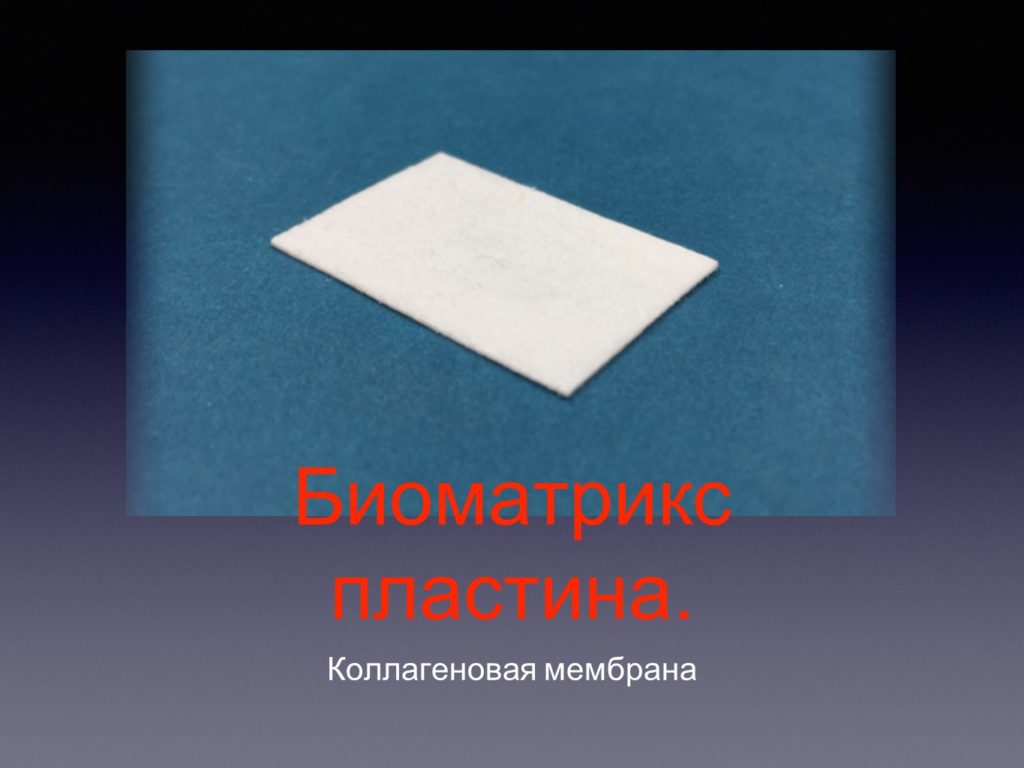

Принцип направленной костной регенерации. Костная регенерация под защитой мембраны Биоматрикс

Принцип направленной костной регенерации. Костная регенерация под защитой мембраны Биоматрикс

Принцип направленной костной регенерации. Костная регенерация под защитой мембраны Биоматрикс